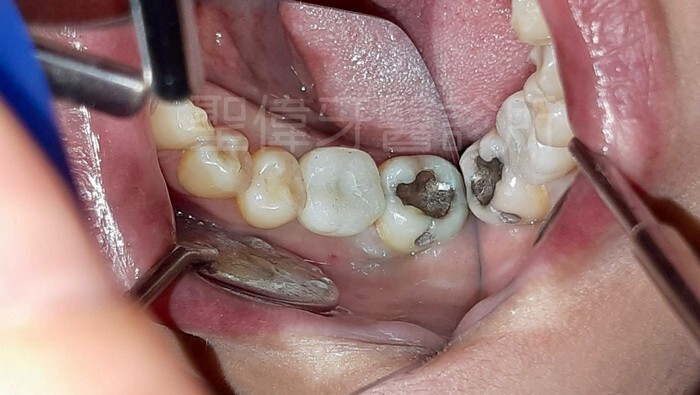

植牙前缺牙的地方

主要也怕如果不做植牙

牙齒旁邊兩顆也會開始晃動